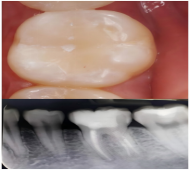

20岁的大学生小林一年前发现后牙出现一个小黑点,因无疼痛感,并未重视。三个月后,进食冷热食物时出现牙齿酸痛,仍未及时就医。直至上周,突发剧烈牙痛,夜间加重难以入睡,来到了西安市红会医院口腔科就诊。经X光片检查,医生发现该“小黑点”已深入牙神经,引发牙髓炎,必须进行根管治疗(俗称“杀神经”),治疗完成后,还需佩戴牙冠保护牙齿。

医生提醒:龋齿初期(只有小黑点、无疼痛)补牙仅需20-30分钟,费用低且无明显不适;一旦侵犯牙神经,不仅治疗复杂,牙齿还会因失去营养变得脆弱。